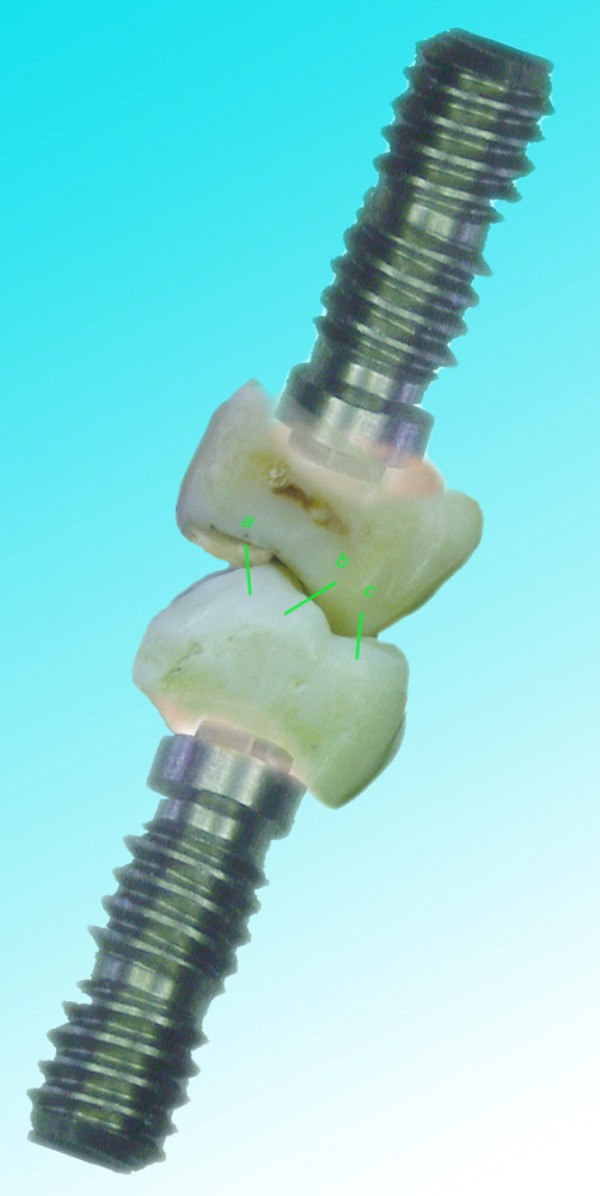

RESUMEN Más allá en el tiempo, respecto de las razones más frecuentes de fracasos como temperatura de fresado, infecciones, falta de fijación inicial, falta de higiene, etc., la OCLUSIÓN recibe sobre sí, la responsabilidad de la permanencia de la osteointegración, como así de la ortofunción del sistema todo. Sometimes ago,conserning the most frecuent reason of failures such as the strawberry action temperature, infections and lack of hygiene…etc.,the OCLUSION has itself the responsability af having the osteointegration well as the allsistem ortofunction . DESARROLLO La valoración de los fracasos en IMPLANTOLOGÍA es difícil de contabilizar sobre todo después del año, ya que el confort logrado por lo general, hace que el paciente realice correctamente sus primeros controles, y después; apoyado en su bienestar; intente subconscientemente olvidar ese período de su vida, que si bien le devolvió su capacidad masticatoria, fonética, social, etc., le ocasionara gastos, molestias, sufrimientos. … la APLICACIÓN de dichas fuerzas, requiere de una exactitud mucho mayor. Los esquemas propuestos a través de los años, no son muchos ni muy variados… I-Evitar las fuerzas tangenciales. II-Repartir las fuerzas lo máximo posible. Sin embargo, muchas veces se confunden los conceptos anteriores con criterios inexactos. Por ej: a-Reducción de las caras vestibulares y palatinas, aceptando que la menor superficie de intercontactos reduce la carga. b-Utilización de la Función de Grupo Posterior, en la creencia de que repartiendo el esfuerzo en las piezas posteriores, ganamos resistencia; a la potencia ejercida por los músculos. c-No permitiendo el contacto excéntrico de un canino implantado, para aliviarlo de las cargas laterales, sobre cargando de esta manera la tabla premolar-molar en el Lado de Trabajo. Algunos conceptos aislados, que forman parte de toda una filosofía de la Oclusión (OCLUSIÓN ORGÁNICA), sean tal vez de ayuda para echar luz sobre los preceptos anteriores. 1º-PROPORCIONES FUNCIONALES DE UN PAR OCLUSAL En la figura siguiente, observamos la relación final masticatoria de un PAR OCLUSAL: En el se ven los contactos puntiformes, producto del choque de superficies redondeadas contra superficies redondeadas («Solo pueden encontrarse en un punto» Ref: Principios Mecánicos Esferoidales.W.Mc.Horris.) Si Miramos con atención este tipo de contactos interoclusales, veremos que la superficie actuante es mucho menor que la superficie total de la cara oclusal: 45% (Fig.1) Por lo tanto, si no es por razones del Pilar de Emergencia para no crear un espacio biológico inadecuado… ¿POR QUÉ REDUCIR LA CARA OCLUSAL VESTÍBULO LINGUALMENTE? (Figs. 2-3-4-5) Si observamos con atención las figuras 2-3-4-5, veremos desde todos los planos , que el área contactante es muy reducida respecto del ancho oclusal total, siendo las fuerzas resultantes , AXIALES al eje implantario. 2º-FUNCIÓN DE GRUPO POSTERIOR. FUNCIÓN CANINA. Tres son las razones por las cuales nos inclinamos a la utilización de la Función Canina. En cambio, en el esquema de FUNCIÓN CANINA, podemos observar que el BRAZO DE POTENCIA, es prácticamente igual al de RESISTENCIA, equilibrando de esta manera la palanca y destruyendo mucho menos las estructuras de soporte(Interface I-H) (Fig. 7) Otra de las razones de peso en este tema es la DIFERENCIA DE ANGULACIÓN que existe entre la cara palatina del canino y las vertientes contactantes del sector premolar-molar. A MAYOR ANGULACIÓN, MENORES FUERZAS LATERALES(Perpendiculares al Plano), y por lo tanto , menor destrucción de la interface Hueso-Implante(Figs. 9-11). DIFERENCIAS EXCITATORIAS DE LOS GRUPOS MUSCULARES. Por último debemos considerar que el intercontacto dentario del sector anterior, estimula excitatoriamente a las fibras anteriores y verticales del temporal (Figs.12-13-14-15), mientras que los contactos posteriores lo hacen con la cincha pterigo-maseterina(Fig. 16-17-18-19) Por lo tanto ,si se comprende el fisiologismo de estos conceptos, es sencillo entender que la sobrecarga de los sectores posteriores es nocivo generando fuerzas tangenciales de Alto Potencial Patológico. 3º-FUNCIÓN DE GRUPO ANTERIOR Las ventajas de un Brazo de Resistencia mayor se acentúan cuando tenemos el esquema de FUNCIÓN DE GRUPO ANTERIOR. Además, debemos tener en cuenta que, durante la función de un Ciclo Masticatorio, es más importante la Desoclusión Final que la Desoclusión Inicial, ya que al ser más larga esta última, es durante el transcurso de su deslizamiento cuando se ejercen fuerzas laterales mayores(Fig. 21) A medida que la punta del canino inferior se acerca a la O.R.C., o sea al Punto de Contacto Intercanino, las fuerzas laterales disminuyen en virtud del acortamiento del brazo de potencia de la palanca, hasta que, al terminar su recorrido, la fuerza es proyectada axialmente sobre el eje del canino superior, debido a que, al margen de la intensidad que la fuerza trae durante el cierre, la dirección de la misma «apunta» en esa dirección. Por eso decimos que los caninos Axializan el Ciclo Masticatorio. Si estamos imitando en lo posible a la naturaleza, no olvidemos este detalle que los dientes naturales provéen, para evitar las fuerzas laterales del canino a la hora de realizar la supraestructura coronaria del mismo. Es ahora menester acentuar que la problemática concreta se manifiesta, no durante la función, sino durante la PARAFUNCIÓN… Cuando estudiamos recorridos de la Dinámica Mandibular, desde el conocido Bicuspoide de Posselt hasta cualquiera de los registros pantográficos, estamos invirtiendo la dirección del movimiento… A.- El primer premolar es el más anterior de la tabla oclusal posterior. Por lo tanto el brazo de resistencia es el mayor de dicha tabla. B.- El lateral, como parte del grupo anterior, cuenta con un empotramiento tipo «clavo largo», y el interseptum lateral -canino, que se opone a la fuerza, es mucho más grueso que la tabla vestibular del primer premolar(Fig.23) C.- Condiciones, las dos anteriores que se favorecen considerablemente, si al enfundar el lateral se logra junto al central una Función de Grupo Anterior. D.- De manera más artificiosa, la instalación de una placa de relajación, soluciona durante la noche lo nocivo de las fuerzas laterales. Veamos un par de casos, como ejemplo de lo dicho: Paciente de 54 años que se presenta a la consulta portando prótesis completa superior y antagonista natural que soporta fundas de porcelana. Obsérvese la función de grupo posterior ejercida, y las consecuencias de la misma: Otro paciente que presenta fractura de la cúspide fundamental de un onlay de porcelana antagonista de cinco piezas implantadas (Fig.27). Radiográficamente se observa la desinserción de uno de sus abuttments cementados (Fig.28). En el Lado de Trabajo (LT), no existe el canino encargado de desocluir la zona afectada (Figs.29-30) Como corolario, cabe entonces una pregunta: ¿Es el Implante en el canino quien debe preservar de patología oclusal al resto del sistema…. ¿Es el Implante…un medio…o un fín? BIBLIOGRAFÍA 1- Dibujos tomados del libro del mismo autor: «OCLUSIÓN ORGÁNICA… UN CAMINO HACIA LA REHABILITACIÓN ORAL»(en preparación) 2- «NEUROFISIOLOGÍA DE LA OCLUSIÓN» 3- «OCLUSIÓN Y FUNCIÓN» 4- «FUNDAMENTOS, TÉCNICAS Y CLÍNICA EN REHABILITACIÓN BUCAL» 5- «OCLUSIÓN Y REHABILITACIÓN» 6- «DISFUNCIÓN TEMPOROMANDIBULAR» 7- «PROCEDIMIENTOS CLÍNICOS Y DE LABORATORIO DE OCLUSIÓN ORGÁNICA» 8- «ESTUDIO ELECTRÓNICO DEL MOVIMIENTO MANDIBULAR» 9- «OCLUSIÓN: CONCEPTO PARA EL CLÍNICO» 10- «IMPLANTOLOGÍA CONTEMPORÁNEA» 11- «OCLUSIÓN Y DIAGNÓSTICO EN REHABILITACIÓN ORAL» 12- «PRINCIPIOS DE OCLUSIÓN»